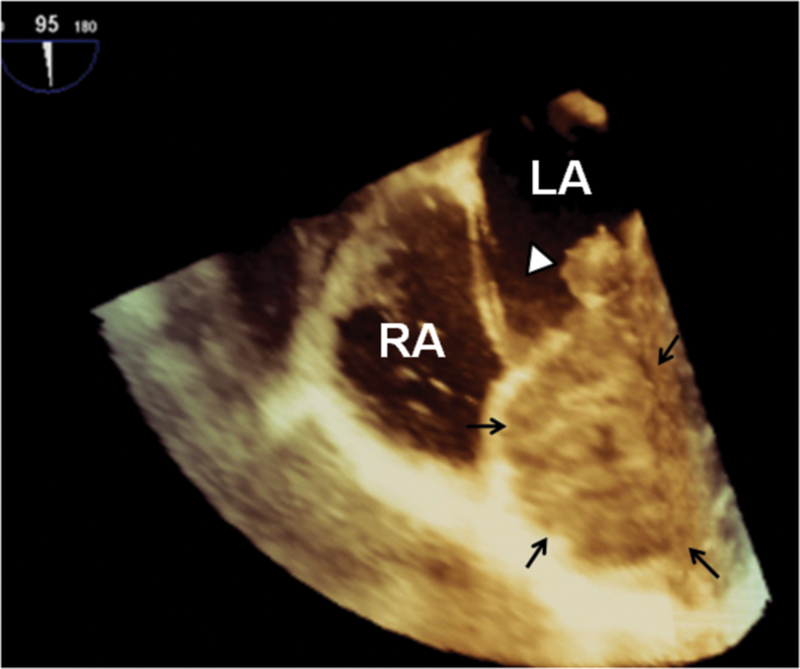

فحوصات تشخيصية لبعض امراض القلب والشرايين التاجية